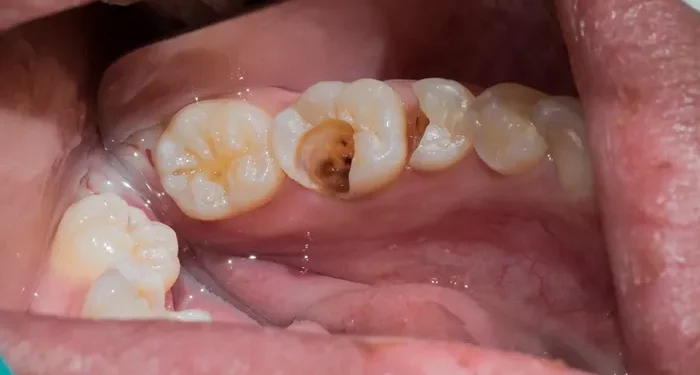

3. Visible Holes or Cavities

When you look in the mirror, you may notice visible holes or dark spots on your teeth. These are often signs of cavities that require fillings. The affected area may appear discolored or have a noticeable indentation. If you observe any such changes, it is important to visit a dentist for a thorough examination and treatment.